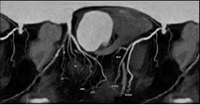

冠脉CTA检查是排查心脏隐患、防范猝死风险的重要手段,也是我们了解自身心脏状况的便捷选择。

检查后,很快就能出具影像诊断结果,清晰呈现心脏血管真实状况,能让隐患无所遁形。

通过冠脉CTA,能清晰地看出多种心脏相关疾病:

最常见的是冠状动脉粥样硬化,也就是常说的“血管变窄”;

还能发现血管内的斑块,判断斑块的大小和稳定性,预警心肌梗死;

还能排查冠脉畸形、血管闭塞等,为临床治疗提供精准依据。